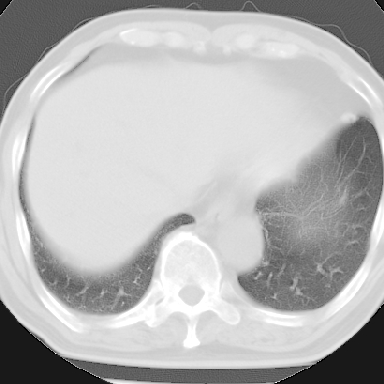

纵隔窗呢?慢支炎肺气肿;余未见明显渗出及占位!

慢性支气管炎、肺气肿。

慢性支气管炎并肺气肿

不支持慢性支气管炎,另外慢性支气管炎的诊断需结合临床病史才能诊断。

就以上的片子,如果没有明确的病史,说未见明显异常也不过份吧

这份病例诊断慢支并气肿可能属过诊,首先慢支的临床诊断标准是严格的,应该弄清楚,其次ct表现是否符合该病表现,本例老年人ct肺窗表现应属正常,不要跟着临床跑。